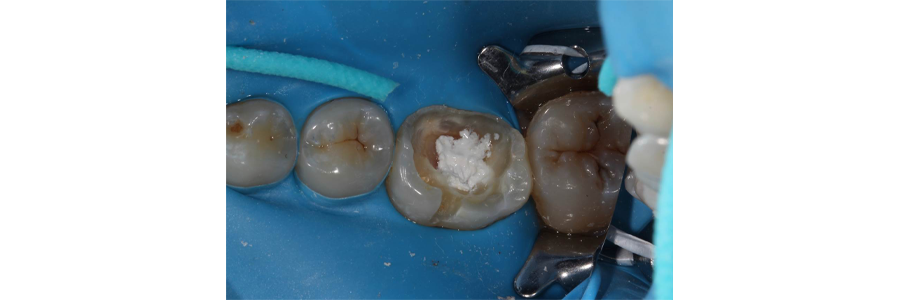

Hemostasis was achieved, and a bioceramic material was placed over the pulp exposure (Fig. 3) and the final restoration of composite was placed (Fig. 4).